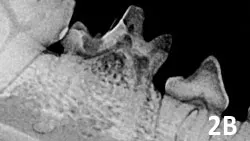

A radiographic image showing the dental structure of a canine jaw, highlighting the roots of the teeth and surrounding bone. The image provides detailed visualization of potential dental pathology, such as periodontal disease or root resorption.

Figure 2B

Type 2 resorption in the deciduous mandibular fourth premolar with exposure to oral cavity; extraction is indicated.

Type 2: There is loss of periodontal ligament space and lamina dura from fusion of tooth root and alveolar bone (ie, dentoalveolar ankylosis). The resorbing tooth structure may appear less radiopaque than the unaffected tooth (ie, replacement resorption). If the lesion extends into the oral cavity (See Figure 2B), using a high-speed water-cooled handpiece the crown can be reduced in height below the gingiva before closure.